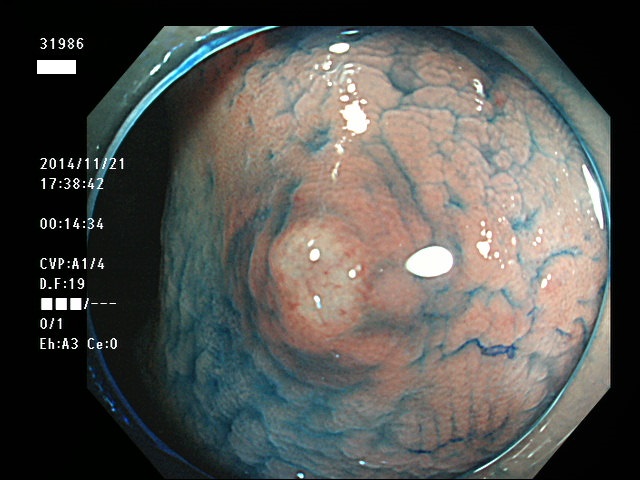

上記100名より抽出した平坦・陥凹型腺腫(=癌化の危険が高いが見落としやすい病変)の内視鏡写真